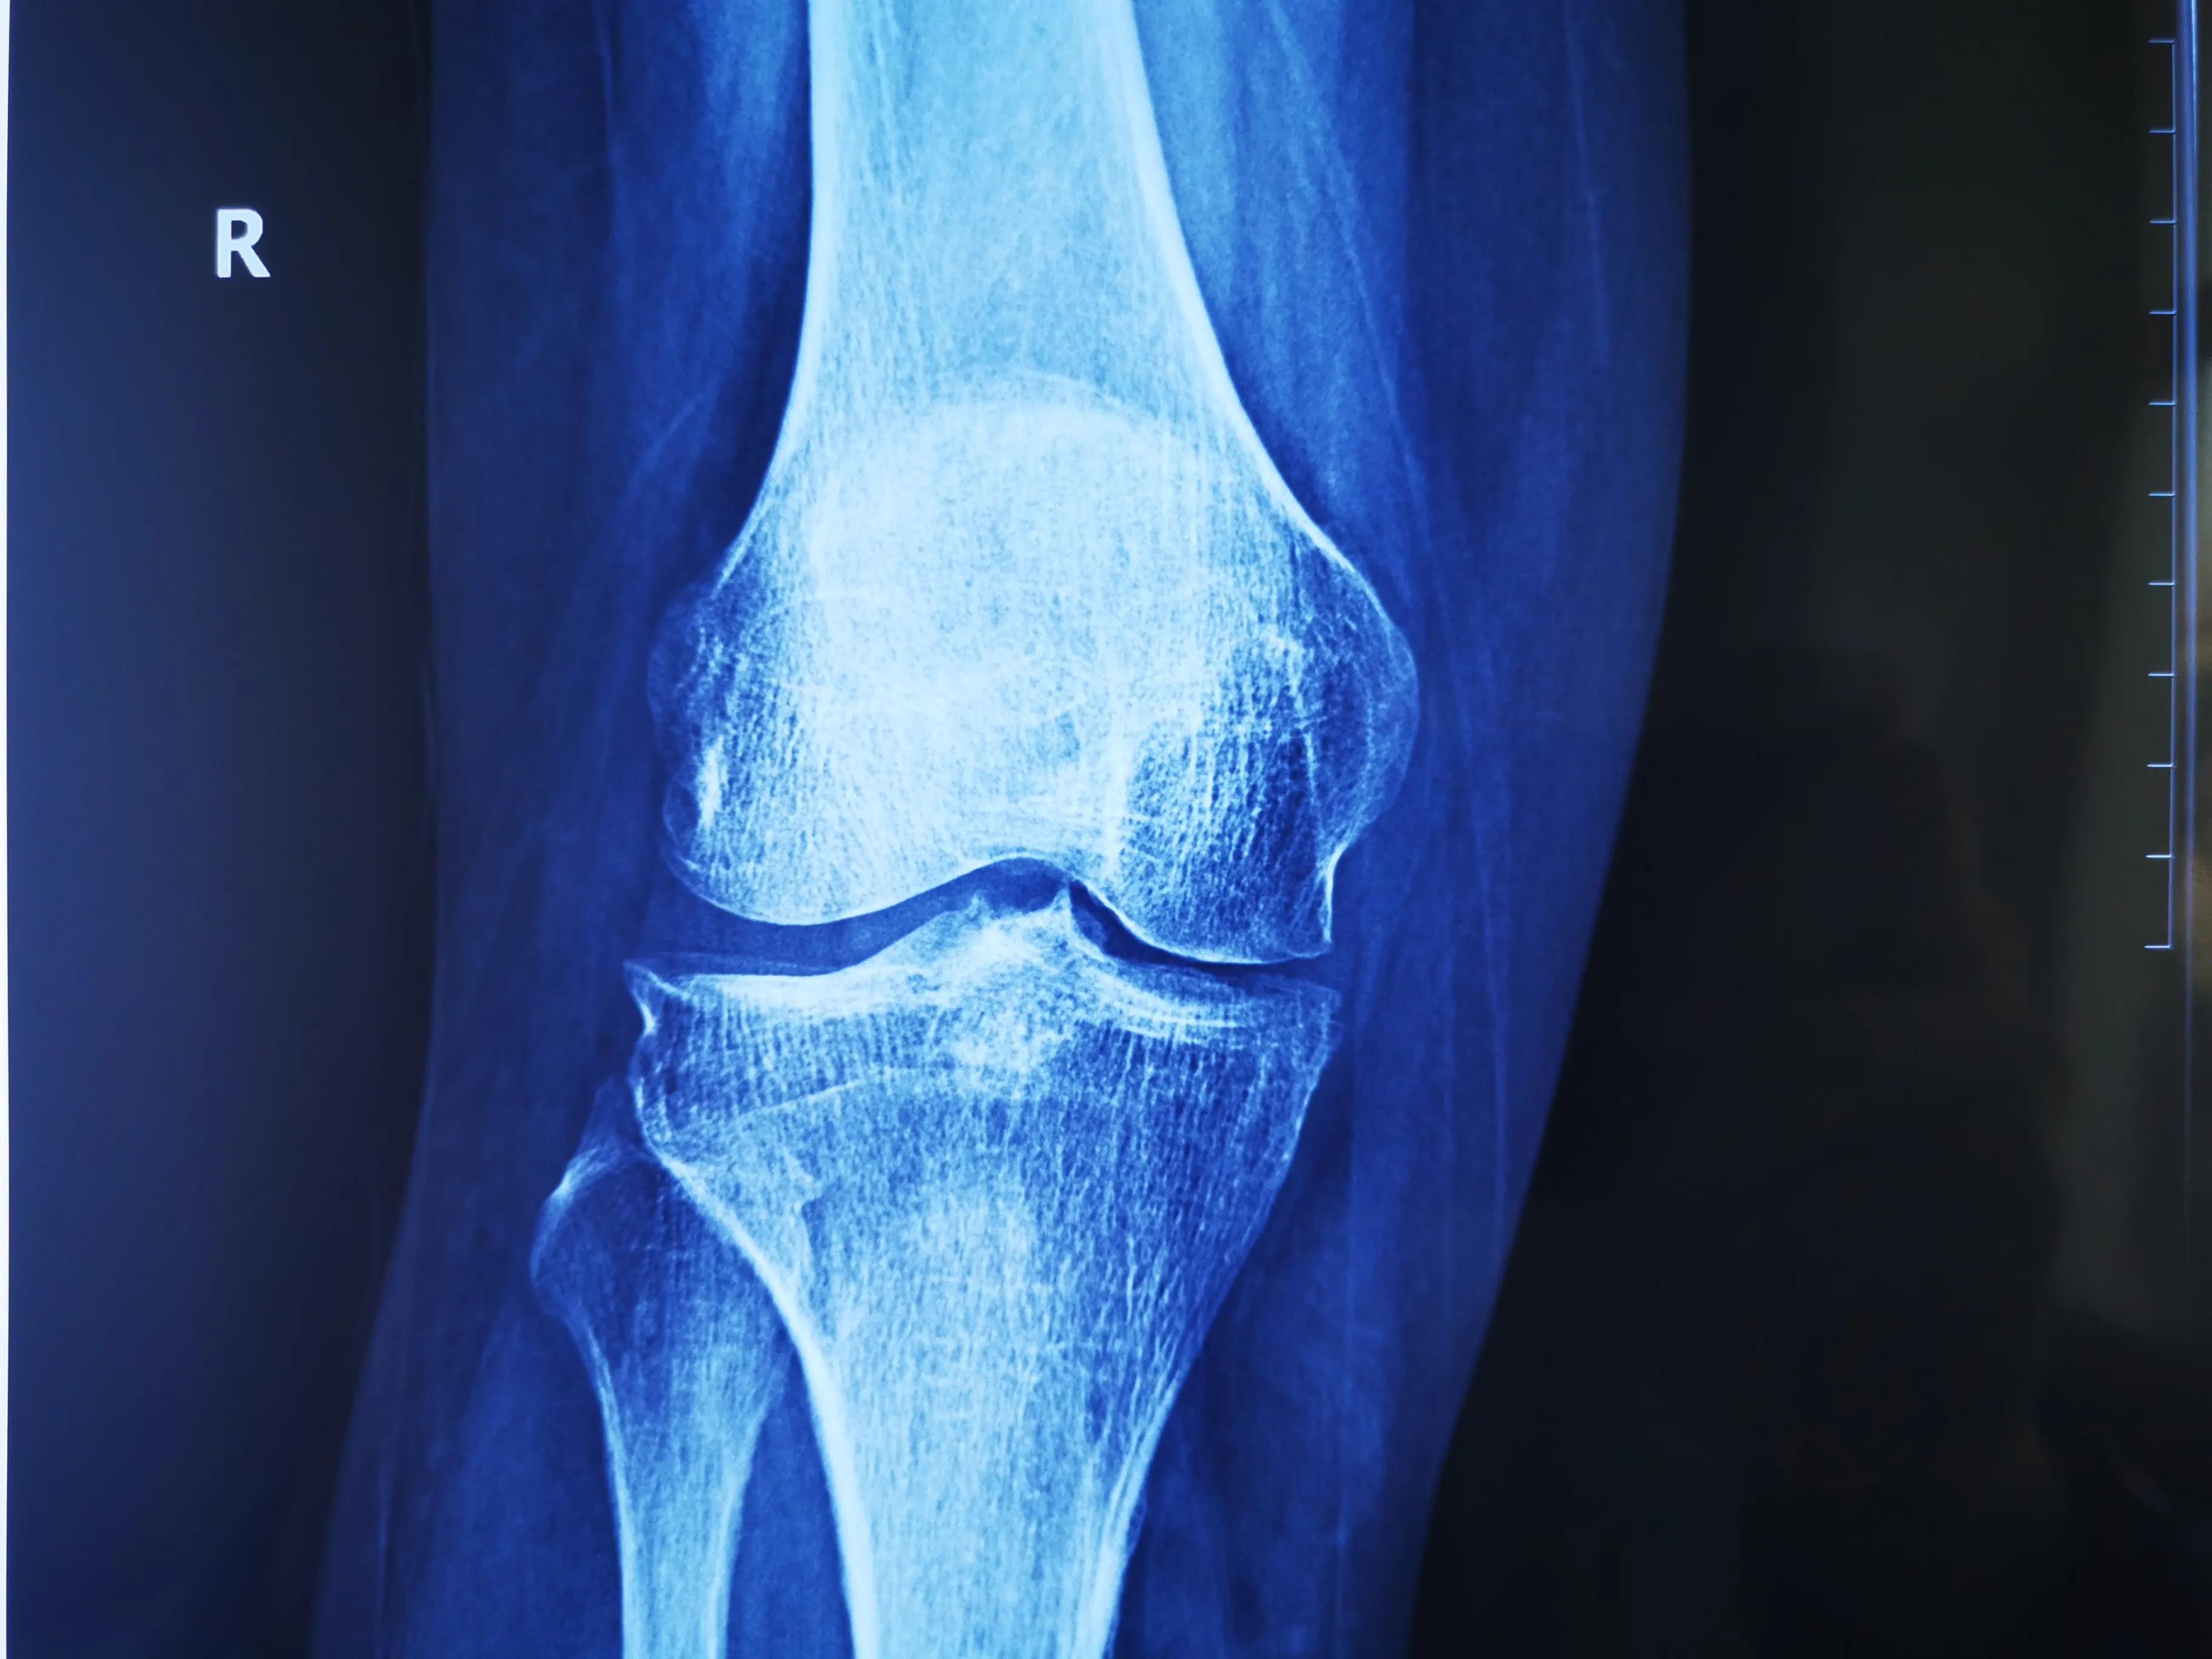

今天一位50多岁的老哥来就诊,就是想做膝盖核磁看看关节的情况,谢医生觉得很奇怪, 为啥没什么事儿要花钱做核磁呢?

老哥说:“ 大夫,我50多岁了,平时工作、运动量挺大,最近感觉关节有疲劳感,我想做个核磁看看关节软骨是否有磨损啊,如果问题不大,我就好好保养关节,我这退休以后还想游遍祖国大好河山呢,膝盖不行了,我啥也干不了了是吧! ”

那么今天正好有时间,我们就借着这位老哥给咱的机会,咱们聊一聊中老年人应该如何保养自己的膝关节。